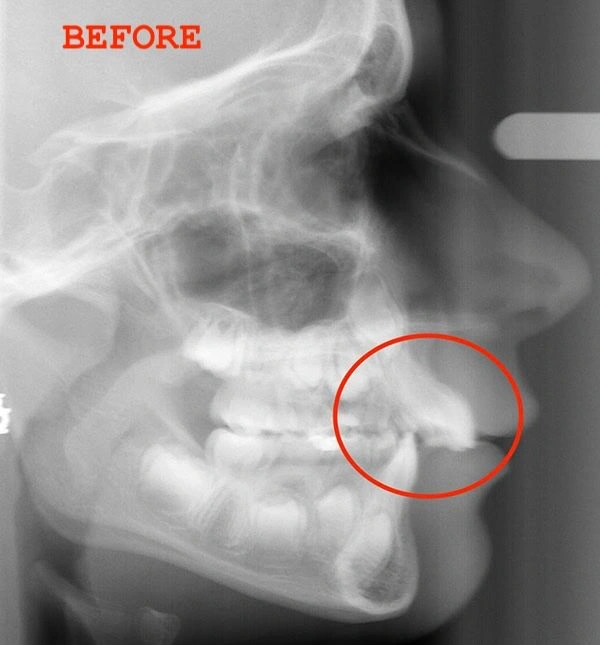

Here’s a common misconception: many parents believe their child’s teeth will improve as they get older. The truth is, if left untreated, conditions like overbites can worsen over time, leading to more severe issues like extractions or even jaw surgery later on. That’s why early treatment—between the ages of 6 and 9—is so important.

Take Kristy, for example. When her daughter, Bailey, came in, we noticed the same overbite problem that headgear would traditionally treat. But instead of resorting to headgear, we tried Invisalign First. The results were nothing short of incredible! Bailey went from hiding her smile to confidently flashing those pearly whites, all without the pain or hassle of headgear.